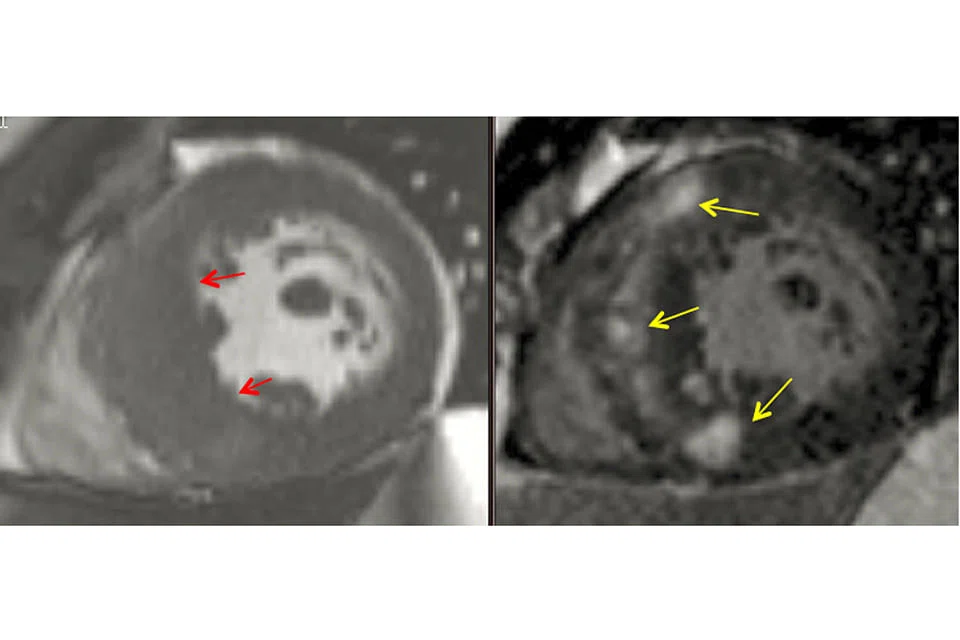

Echocardiogram and Cardiovascular Magnetic Resonance Imaging (CMR) can be used to assess and monitor the heart function, the severity of LVOT obstruction and the changes of the wall thickness of the heart muscle. CMR has the advantage of being able to detect the heart muscle damage (fibrosis) due to HCM with contrast medium administration (Figure 1). In addition, CMR can reliably assess the regional heart muscle thickening not clearly visualised by echocardiogram.